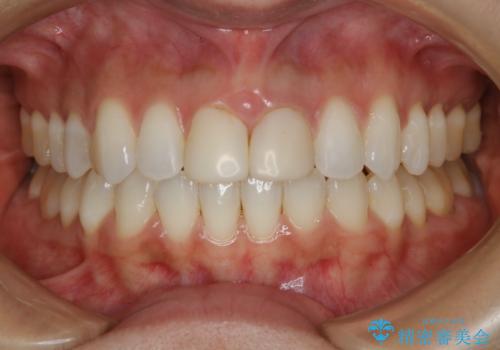

- 前歯のガタつきの改善を主訴に来院された患者様です。

ガタつきによる上顎正中の空隙や歯の突出感も気にされていました。

費用を抑えたいとの事だったので歯の移動量なども考慮し、インビザライン・ライトパッケージでの治療を計画しました。

インビザライン・ライトパッケージでは歯の移動量が限られている分、費用と期間を抑えて治療することが出来ます。